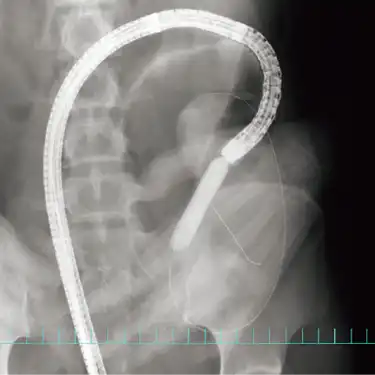

狭窄部に対する内視鏡拡張術 -

病気の予後はいかに早期に発見し腸の状態をよくできるかで決まるとされますが、進行した状態でも治療薬や外科手術、内視鏡手術の進歩により生活の質を向上できる患者さんが増えています。とりわけ2002年から使用可能となった生物学的製剤(注射薬)により大幅に予後が改善しており、最近では副作用と効果のバランスに優れた治療薬も使用可能となっています。